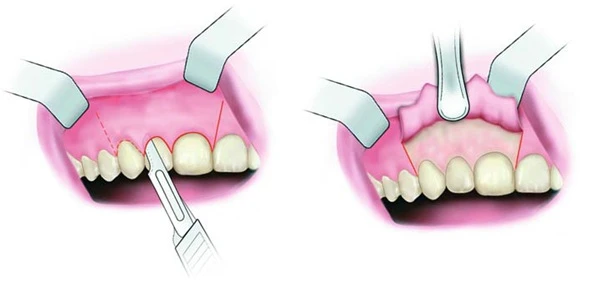

1.Vạt hình thang

Được thiết kế như hình vẽ dưới đây, vạt đi qua gai nướu của hai răng lân cận và đi trong rãnh đường viền nướu. Lật vạt toàn phần bộc lộ xương vùng chóp răng.

Vạt hình thang